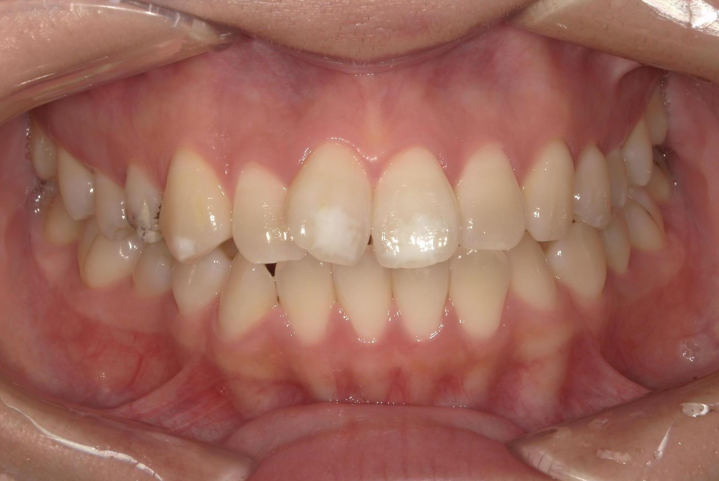

年齢 20代女性

主訴

上顎前突

前歯叢生

治療期間 2024年3月~25年12月

矯正種類 マウスピース矯正(クリアコレクト)

AFTER